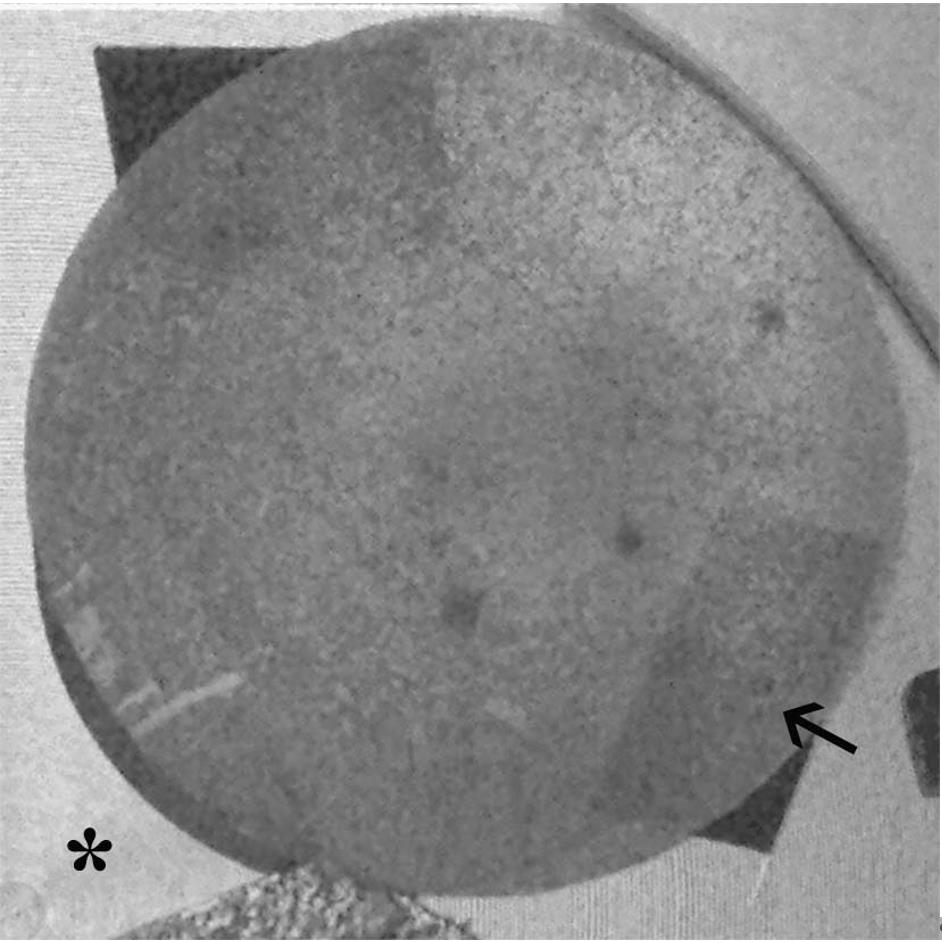

Deposit 40 μL of SF samples on the aluminum stub previously covered with a conductive carbon adhesive disk and incubate the sample (Figure 2) in a humid chamber at 4 °C for 24–48 h before the analysis.

Note: The ESEM analysis of the elements present in the synovial fluid is a simple technique, as the samples are deposited without any type of treatment on the stub and observed after overnight incubation.

4. Evaluate the central stub area considering the area with a diffuse presence of the crystal, excluding big crystal aggregates. Prepare the samples under complete sterility, changing the pipette for each sample.

5. Collect the morphometric data (number, size, and morphology) of all visible particles in the reference area through accurate observations and measurements in several ESEM images. For image analysis, use Photoshop and ImageJ software.

6. Select the images following two main criteria: (i) to be representative of the total area of each sample examined and (ii) to have a significant number of measurements. Examples of background images (Figure 3) and particles (Figure 4) are shown in Figure 3A and 3B.

Note: In the different single areas, examples of electrodense particles: 1) small particles with sizes ranging from 20 to 80 nm (not only calcium but also phosphate, sulfur, and potassium) in Figure 3; 2) big calcium particles with dimensions between 2 and 10 μm in Figure 4.